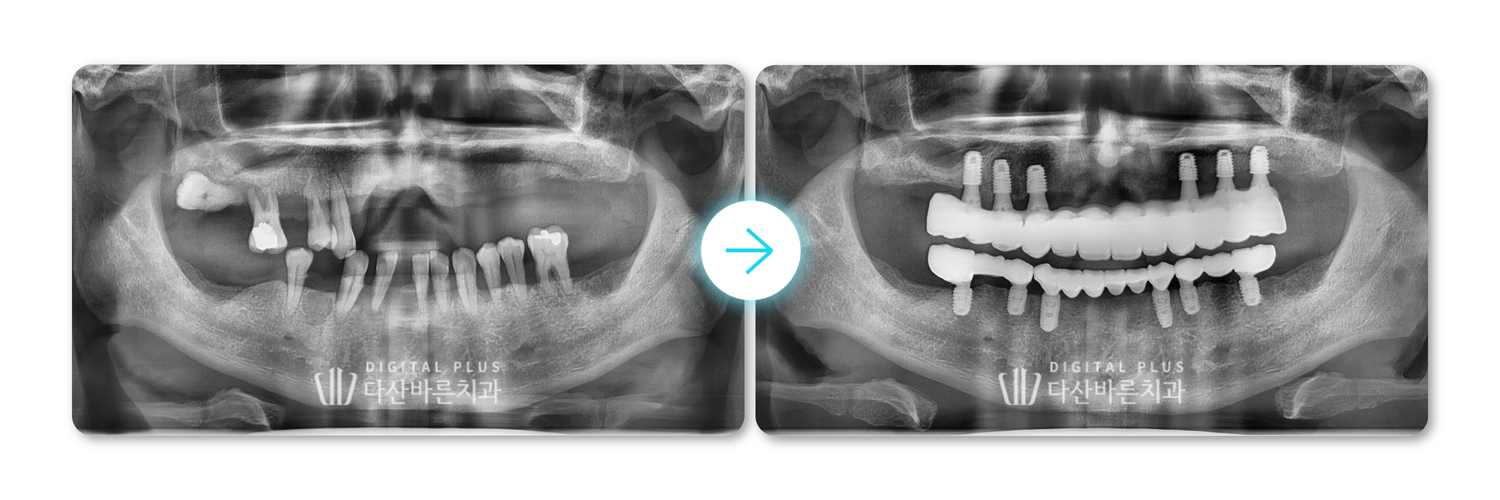

[환자 연령] 40대

[내원 사유] 치아가 몇 개 안 남고 나머지도 흔들려요.

[치료 내용] 상·하악 디지털 풀아치 임플란트